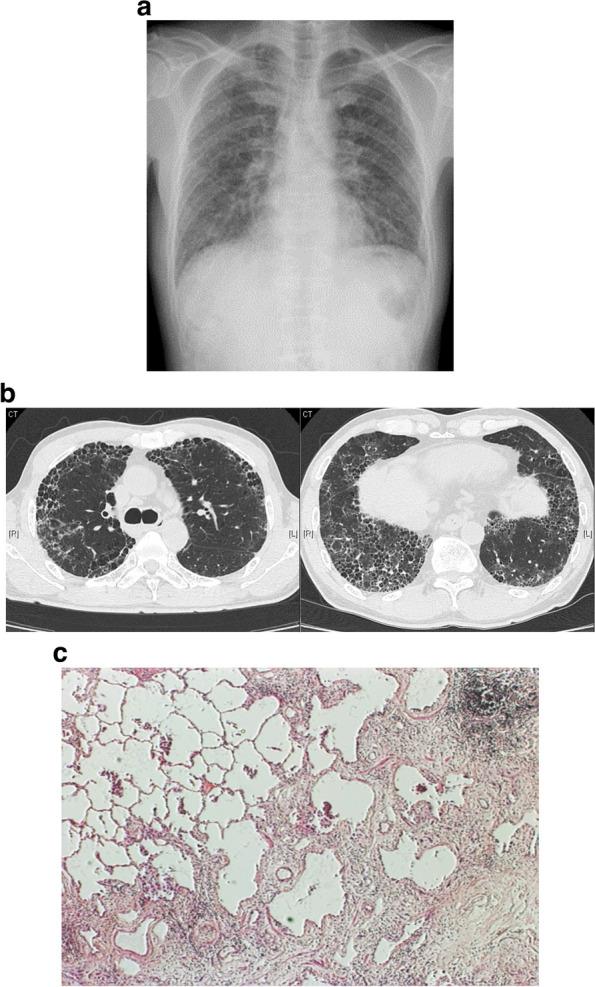

Interstitial lung diseases (ILDs) are a diverse group of conditions characterized by inflammation and fibrosis in the lung. In some patients with ILD, a progressive fibrotic phenotype develops, which is associated with an irreversible decline in lung function and a poor prognosis.

The pathological mechanisms that underlie this process culminate in fibroblast activation, proliferation, and differentiation into myofibroblasts, which deposit extracellular matrix proteins and result in fibrosis. Upstream of fibroblast activation, epithelial cell injury and immune activation are known initiators of fibrosis progression, with multiple diverse cell types involved. Recent years have seen an increase in our understanding of the complex and interrelated processes that drive fibrosis progression in ILD, in part due to the advent of single-cell RNA sequencing technology and integrative multiomics analyses. Novel pathological mechanisms have been identified, which represent new targets for drugs currently in clinical development. These include phosphodiesterase 4 inhibitors and other molecules that act on intracellular cyclic adenosine monophosphate signaling, as well as inhibitors of the autotaxin-lysophosphatidic acid axis and   integrins. Here, we review current knowledge and recent developments regarding the pathological mechanisms that underlie progressive fibrotic ILD, including potential therapeutic targets.

Knowledge of the pathological mechanisms that drive progressive fibrosis in patients with ILD has expanded, with the role of alveolar endothelial cells, the immune system, and fibroblasts better elucidated. Drugs that target novel mechanisms hold promise for expanding the future therapeutic armamentarium for progressive fibrotic ILD.

间质性肺疾病(ILDs)是一组多样的疾病,其特征为肺部炎症和纤维化。在一些ILD患者中,会出现进行性纤维化表型,这与肺功能不可逆下降及预后不良相关。

这一过程背后的病理机制最终导致成纤维细胞活化、增殖并分化为肌成纤维细胞,后者沉积细胞外基质蛋白并导致纤维化。在成纤维细胞活化的上游,上皮细胞损伤和免疫激活是已知的纤维化进展启动因素,涉及多种不同细胞类型。近年来,我们对驱动ILD纤维化进展的复杂且相互关联的过程的理解有所增加,部分原因是单细胞RNA测序技术和综合多组学分析的出现。已确定了新的病理机制,这些机制代表了目前正在临床开发的药物的新靶点。这些包括磷酸二酯酶4抑制剂和其他作用于细胞内环磷酸腺苷信号传导的分子,以及自分泌运动因子-溶血磷脂酸轴和整合素的抑制剂。在此,我们综述了关于进行性纤维化ILD潜在病理机制的现有知识和最新进展,包括潜在治疗靶点。

对驱动ILD患者进行性纤维化的病理机制的认识有所扩展,肺泡内皮细胞、免疫系统和成纤维细胞的作用得到了更好的阐明。针对新机制的药物有望为未来进行性纤维化ILD的治疗手段增添新的武器。